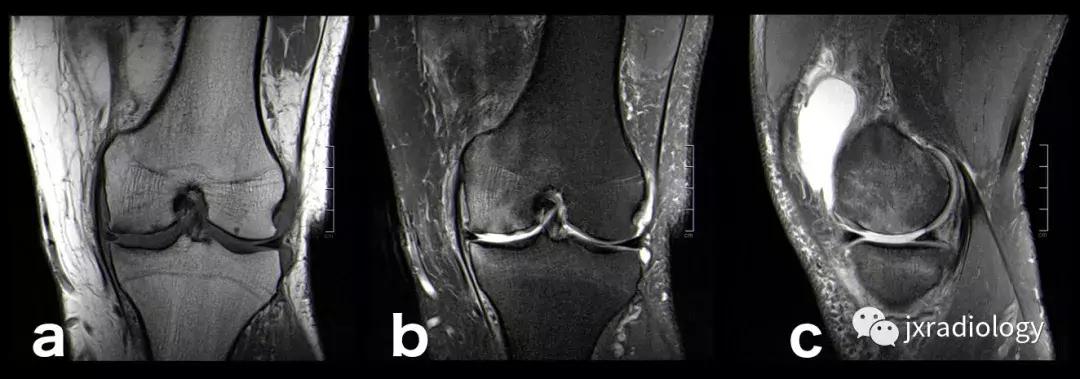

图2:骨性关节炎(OA):男,58岁,股骨内侧髁负重区有软骨缺损,伴有边缘小骨赘和继发性软骨下骨髓水肿。 骨性关节炎通常不与创伤性病因分类,而是作为退行性病变分类(a:冠状T1-WI; b:冠状PDWI-FS; c:矢状PDWI-FS)。